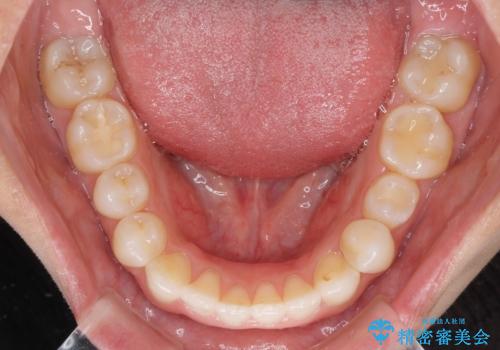

- 上下の前歯のデコボコと奥歯の反対咬合を気にして来院された患者様です。

インビザラインを用い、上下顎ともにIPR(歯と歯の間を削る)により叢生を改善することとしました。

治療を長期化させたくないとのご要望があったので、左下の90度捻転した歯は、捻転した状態のゴールとしました。